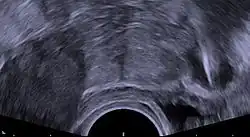

| Transvaginal ultrasonography showing a foreign body granuloma at right as a hypoechoic (dark) area around a perforated intrauterine device. The uterus is at left. | |